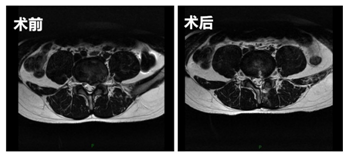

患者小翟是个20岁的年轻小伙子,来我院就诊时,左下肢疼痛难忍活动受限,一直卧床休息,严重影响了生活质量,主诊医师陈海龙团队接诊后,为小翟完善相关检查,诊断为L4/L5椎间盘突出,又经过详细的术前评估,最后决定利用UBE技术为患者减轻痛苦。术后患者疼痛症状消失,第二天便可以下床活动。

UBE技术即单侧双通道内镜技术(unilateral biportal endoscopic technique),适用于颈椎、胸椎、腰椎的退行性变,是一种新兴的脊柱微创手术技术。与椎间孔镜的单通道不同,该技术通常建立两通道,一个为观察通道,一个器械操作通道。观察通道一般用0度或30度关节镜,操作通道可以应用常规的脊柱外科及运动医学的器械如刮匙、磨钻(关节镜磨头)、关节镜刨刀、关节镜射频刀头、椎板咬骨钳、髓核钳、神经拉钩等,两个通道的操作互不干扰,使脊柱微创手术的操作更加便捷灵活。

此外,相对于传统的切口手术,UBE技术手术时仅有两个长约1cm的小切口,创伤明显减少,术中出血少,背部肌群损伤小,术后效果立竿见影,减少了并发症的发生,缩短了患者的住院时间,很大程度上帮助了患者早日回归正常生活。